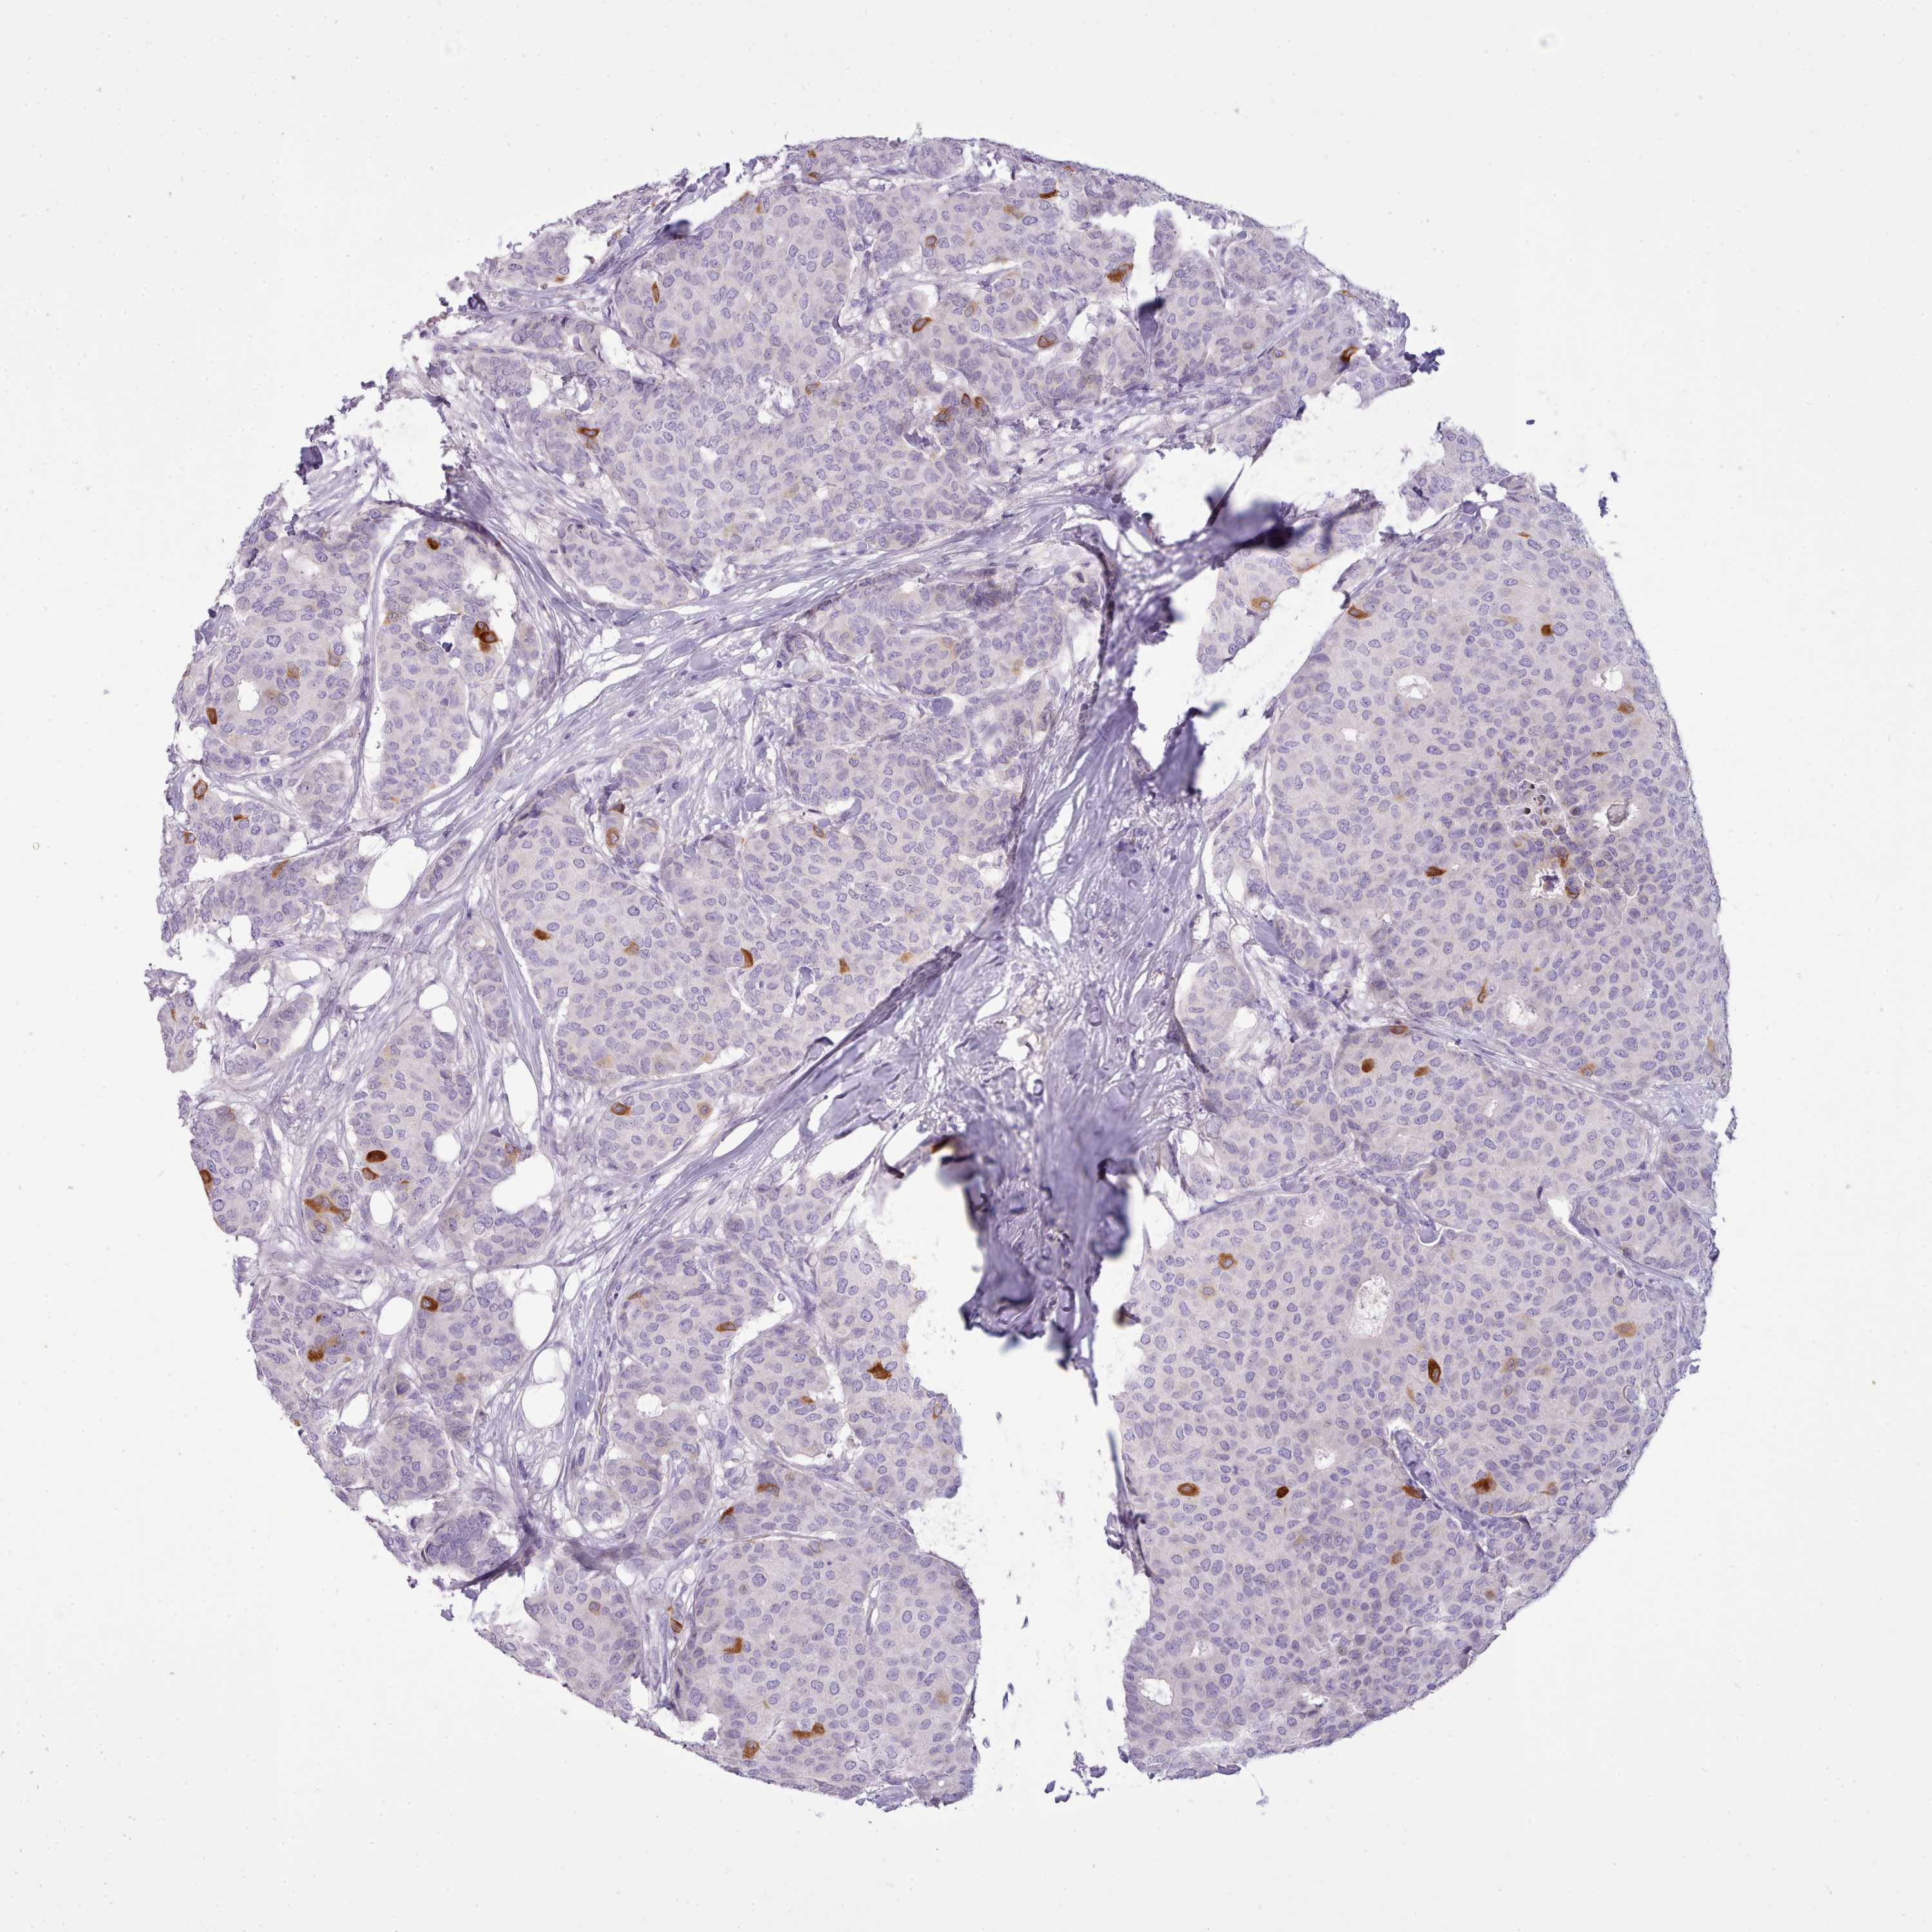

CANCER BREAST CANCER Show tissue menu

BRCA TCGA BRCA VALIDATION PROTEIN EXPRESSION

ANTIBODIES

AND

VALIDATION